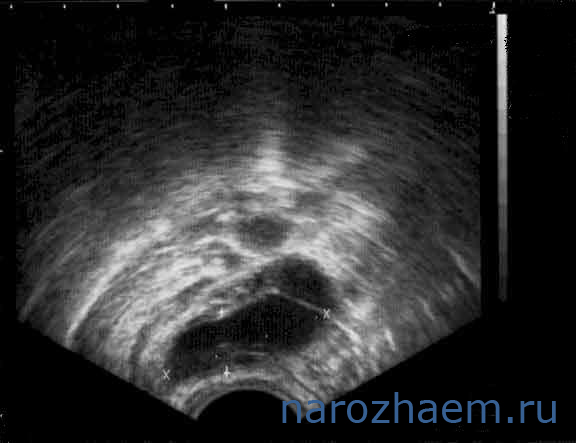

Диагностировать гидросальпинкс можно с помощью УЗИ

Патология не всегда поддаётся диагностике. При простом осмотре врач сможет заметить недуг только в запущенном состояние. Гинеколог назначает ультразвуковое исследование, рентген трубчатого органа. УЗИ покажет, есть ли жидкость, а ГСГ определит уровень непроходимости. Лапароскопия – один из методов лечения и обследования гидросальпинкса.